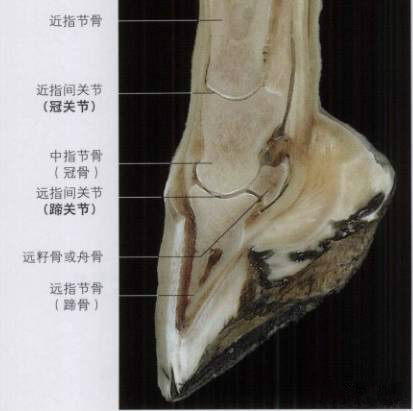

小小的蹄子里面有骨骼、关节、肌腱、腱鞘、韧带、软骨等结构,这些结构对蹄的功能都是非常重要的,任何一个损伤都会产生跛行,甚至有可能出现严重的后果。